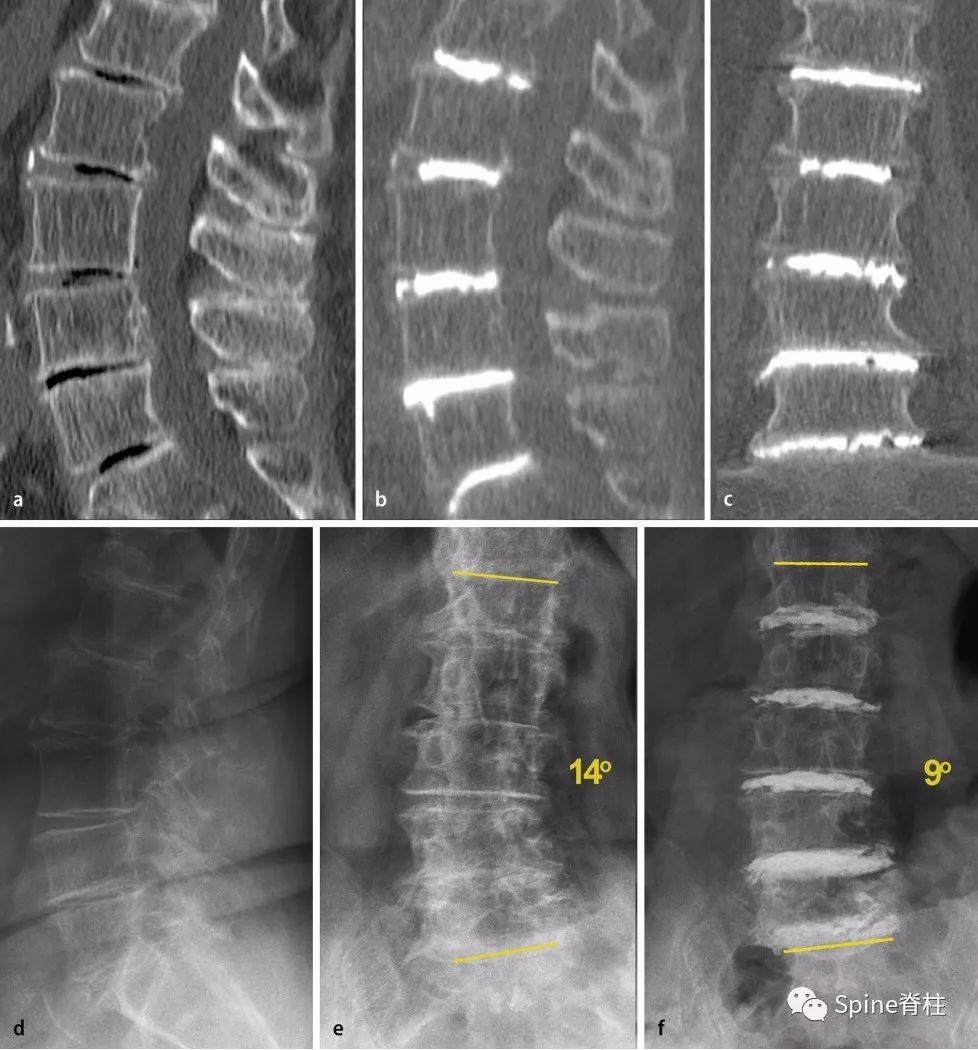

图四:5个节段PCD

a:腰椎的术前CT矢状位重建。多节段椎间盘退变,所有椎间隙均有真空征。

-

b,c:5个节段PCD后的水泥位置。术后CT矢状面和冠状重建情况。

d,e:术前站立位的X光片,侧位和正位。

f:术后站立位正位X片,可观察到PCD所致退行性脊柱侧凸的中度矫正。